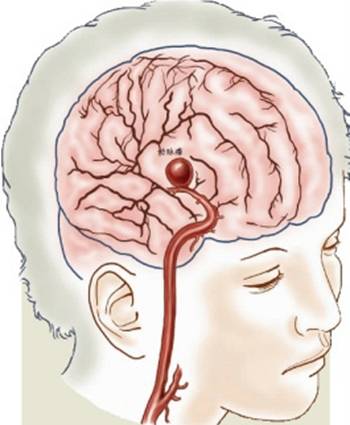

颅内动脉瘤85%发生于前循环,其中前交通动脉(30-35%)、颈内动脉-后交通动脉(30-35%)、大脑中动脉分叉(20%);15%发生于后循环,其中基底动脉占5%,10%发生于其他后颅窝血管。

平扫—般为圆形、葫芦形或条形稍高密度影,动脉瘤壁有钙化时,CT易于显示。如动脉瘤破裂出血则表现为蛛网膜下腔出血,平扫是瘤体不易显示时,需要行CTA扫描。

属于介入治疗方法,采取经皮穿刺股(或颈)动脉,插入导引管,再经导引管插入微导管至动脉瘤内或载瘤动脉,经微导管送入栓塞材料(如球囊、微弹簧圈),将动脉瘤或载瘤动脉闭塞的方法。–此方法创伤小、效果佳、术后恢复快。